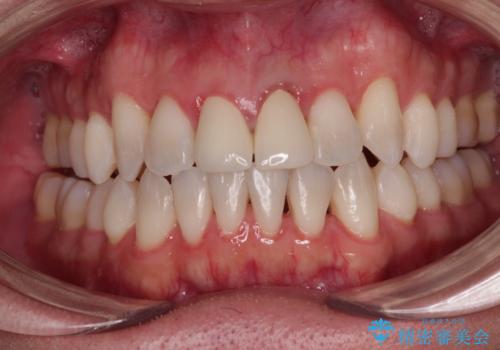

インビザラインでの矯正治療がそろそろ終了とのことで、新しいインビザラインセットを発注する前に気になっている前歯2本をオールセラミッククラウンにて補綴治療を行うこととしました。

歯肉の腫脹は大分改善されましたが、なかなかご自身でのブラッシングが上達せず、やや腫脹残った状態での治療終了となりました。